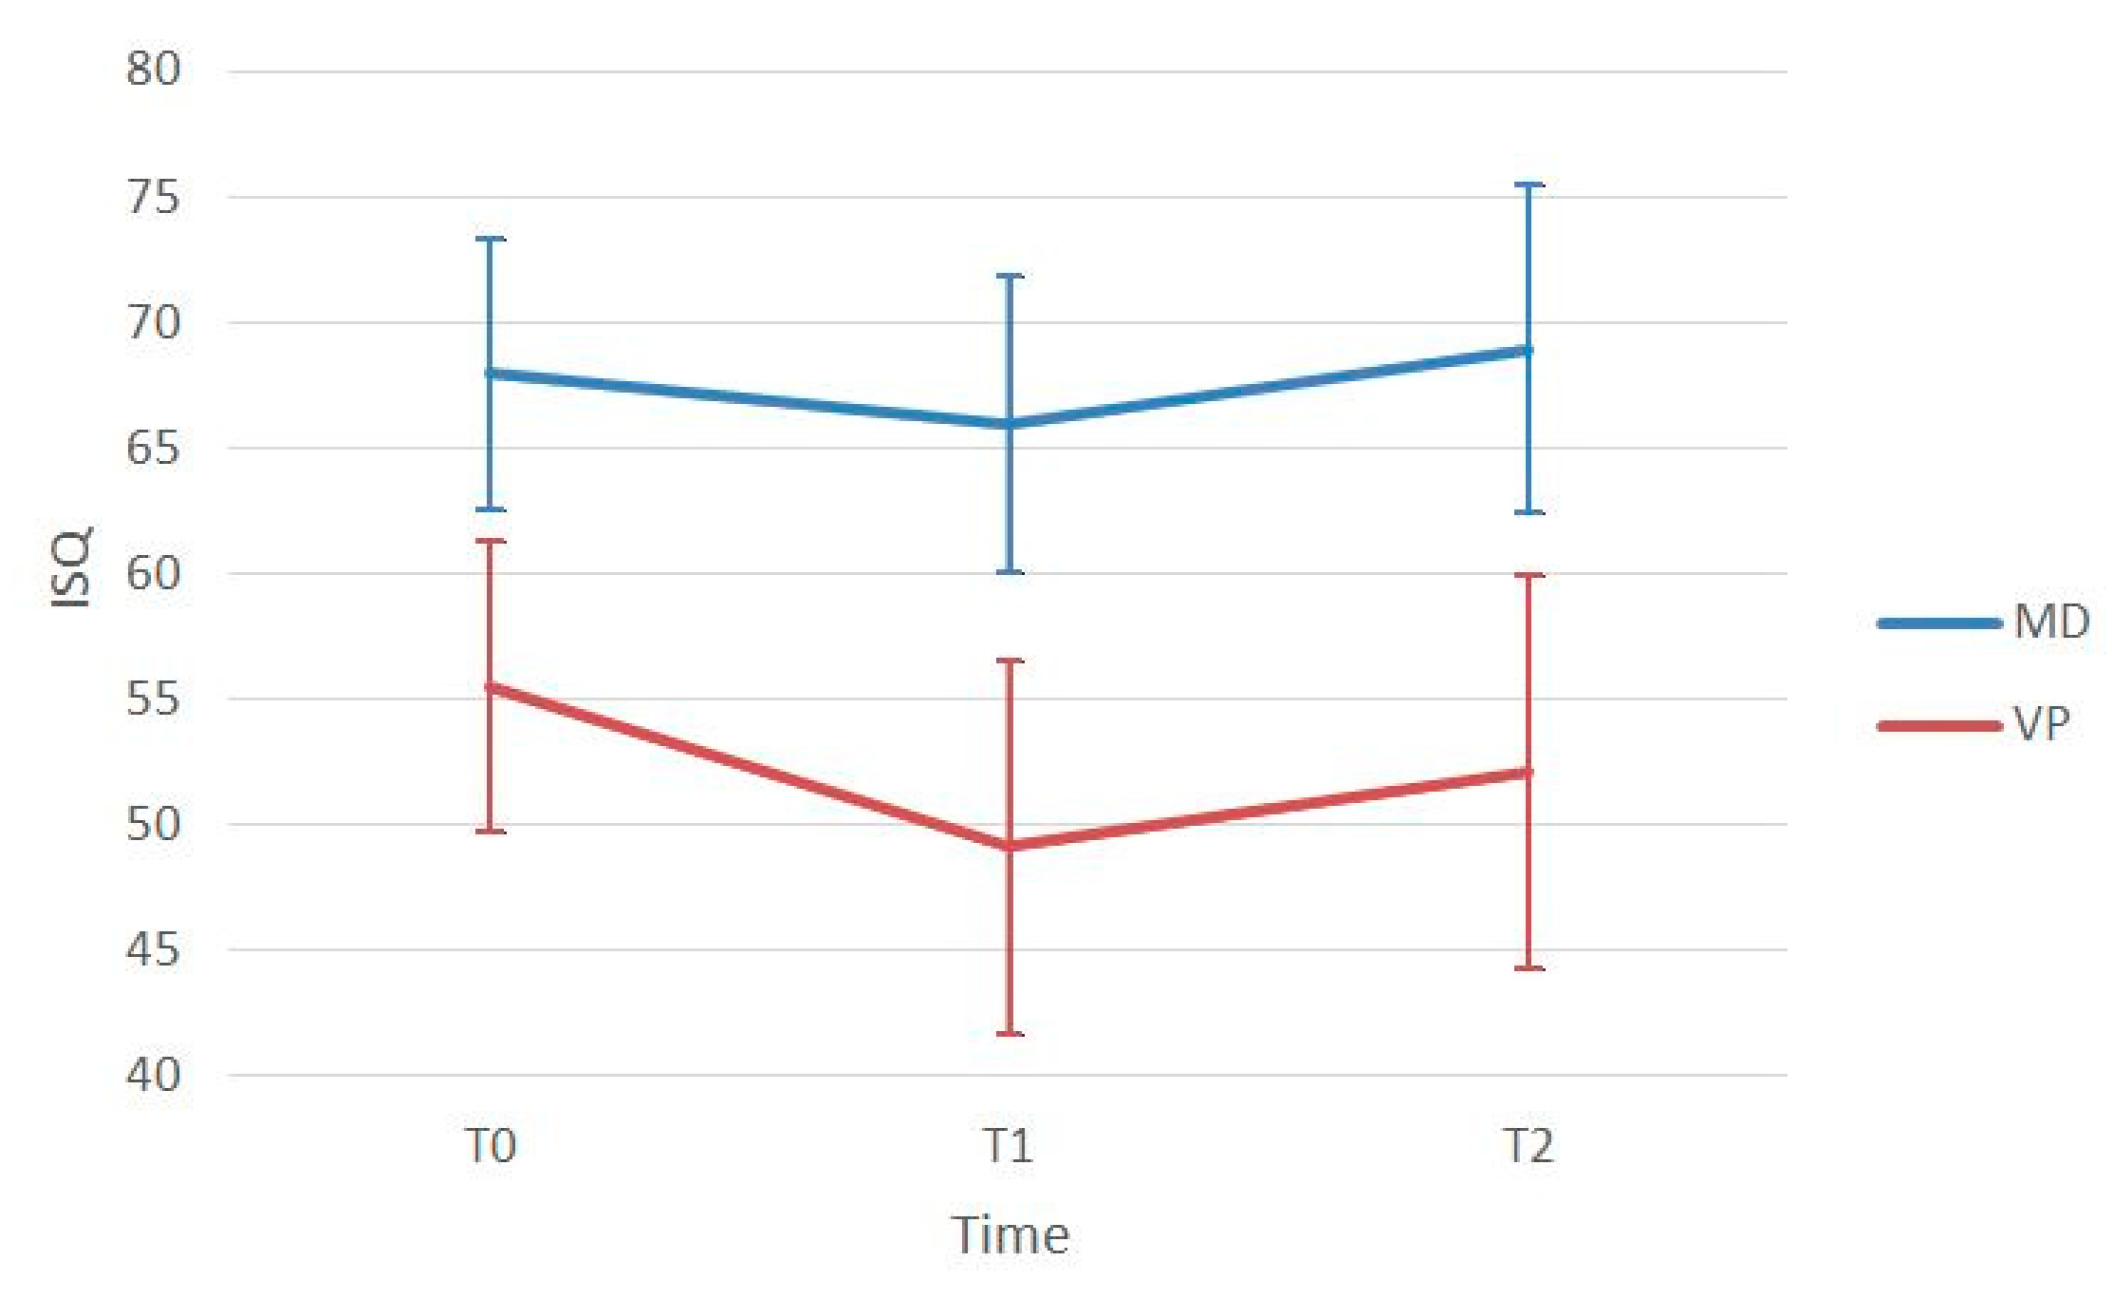

| ISQ T0 | ISQ T1 | T1-T0 (p-Value) | ISQ T2 | T2-T0 (p-Value) | T2-T1 (p-Value) | |

|---|---|---|---|---|---|---|

| Mesio-Distal | 67.96 ± 5.41 | 65.93 ± 5.71 | 0.007 * | 68.93 ± 6.51 | 0.727 | <0.001 * |

| Bucco-Lingual | 55.48 ± 5.79 | 49.12 ± 7.47 | <0.001 * | 52.10 ± 7.79 | 0.004 * | <0.001 * |

| p-value | <0.001 * | <0.001 * | < 0.001 * |